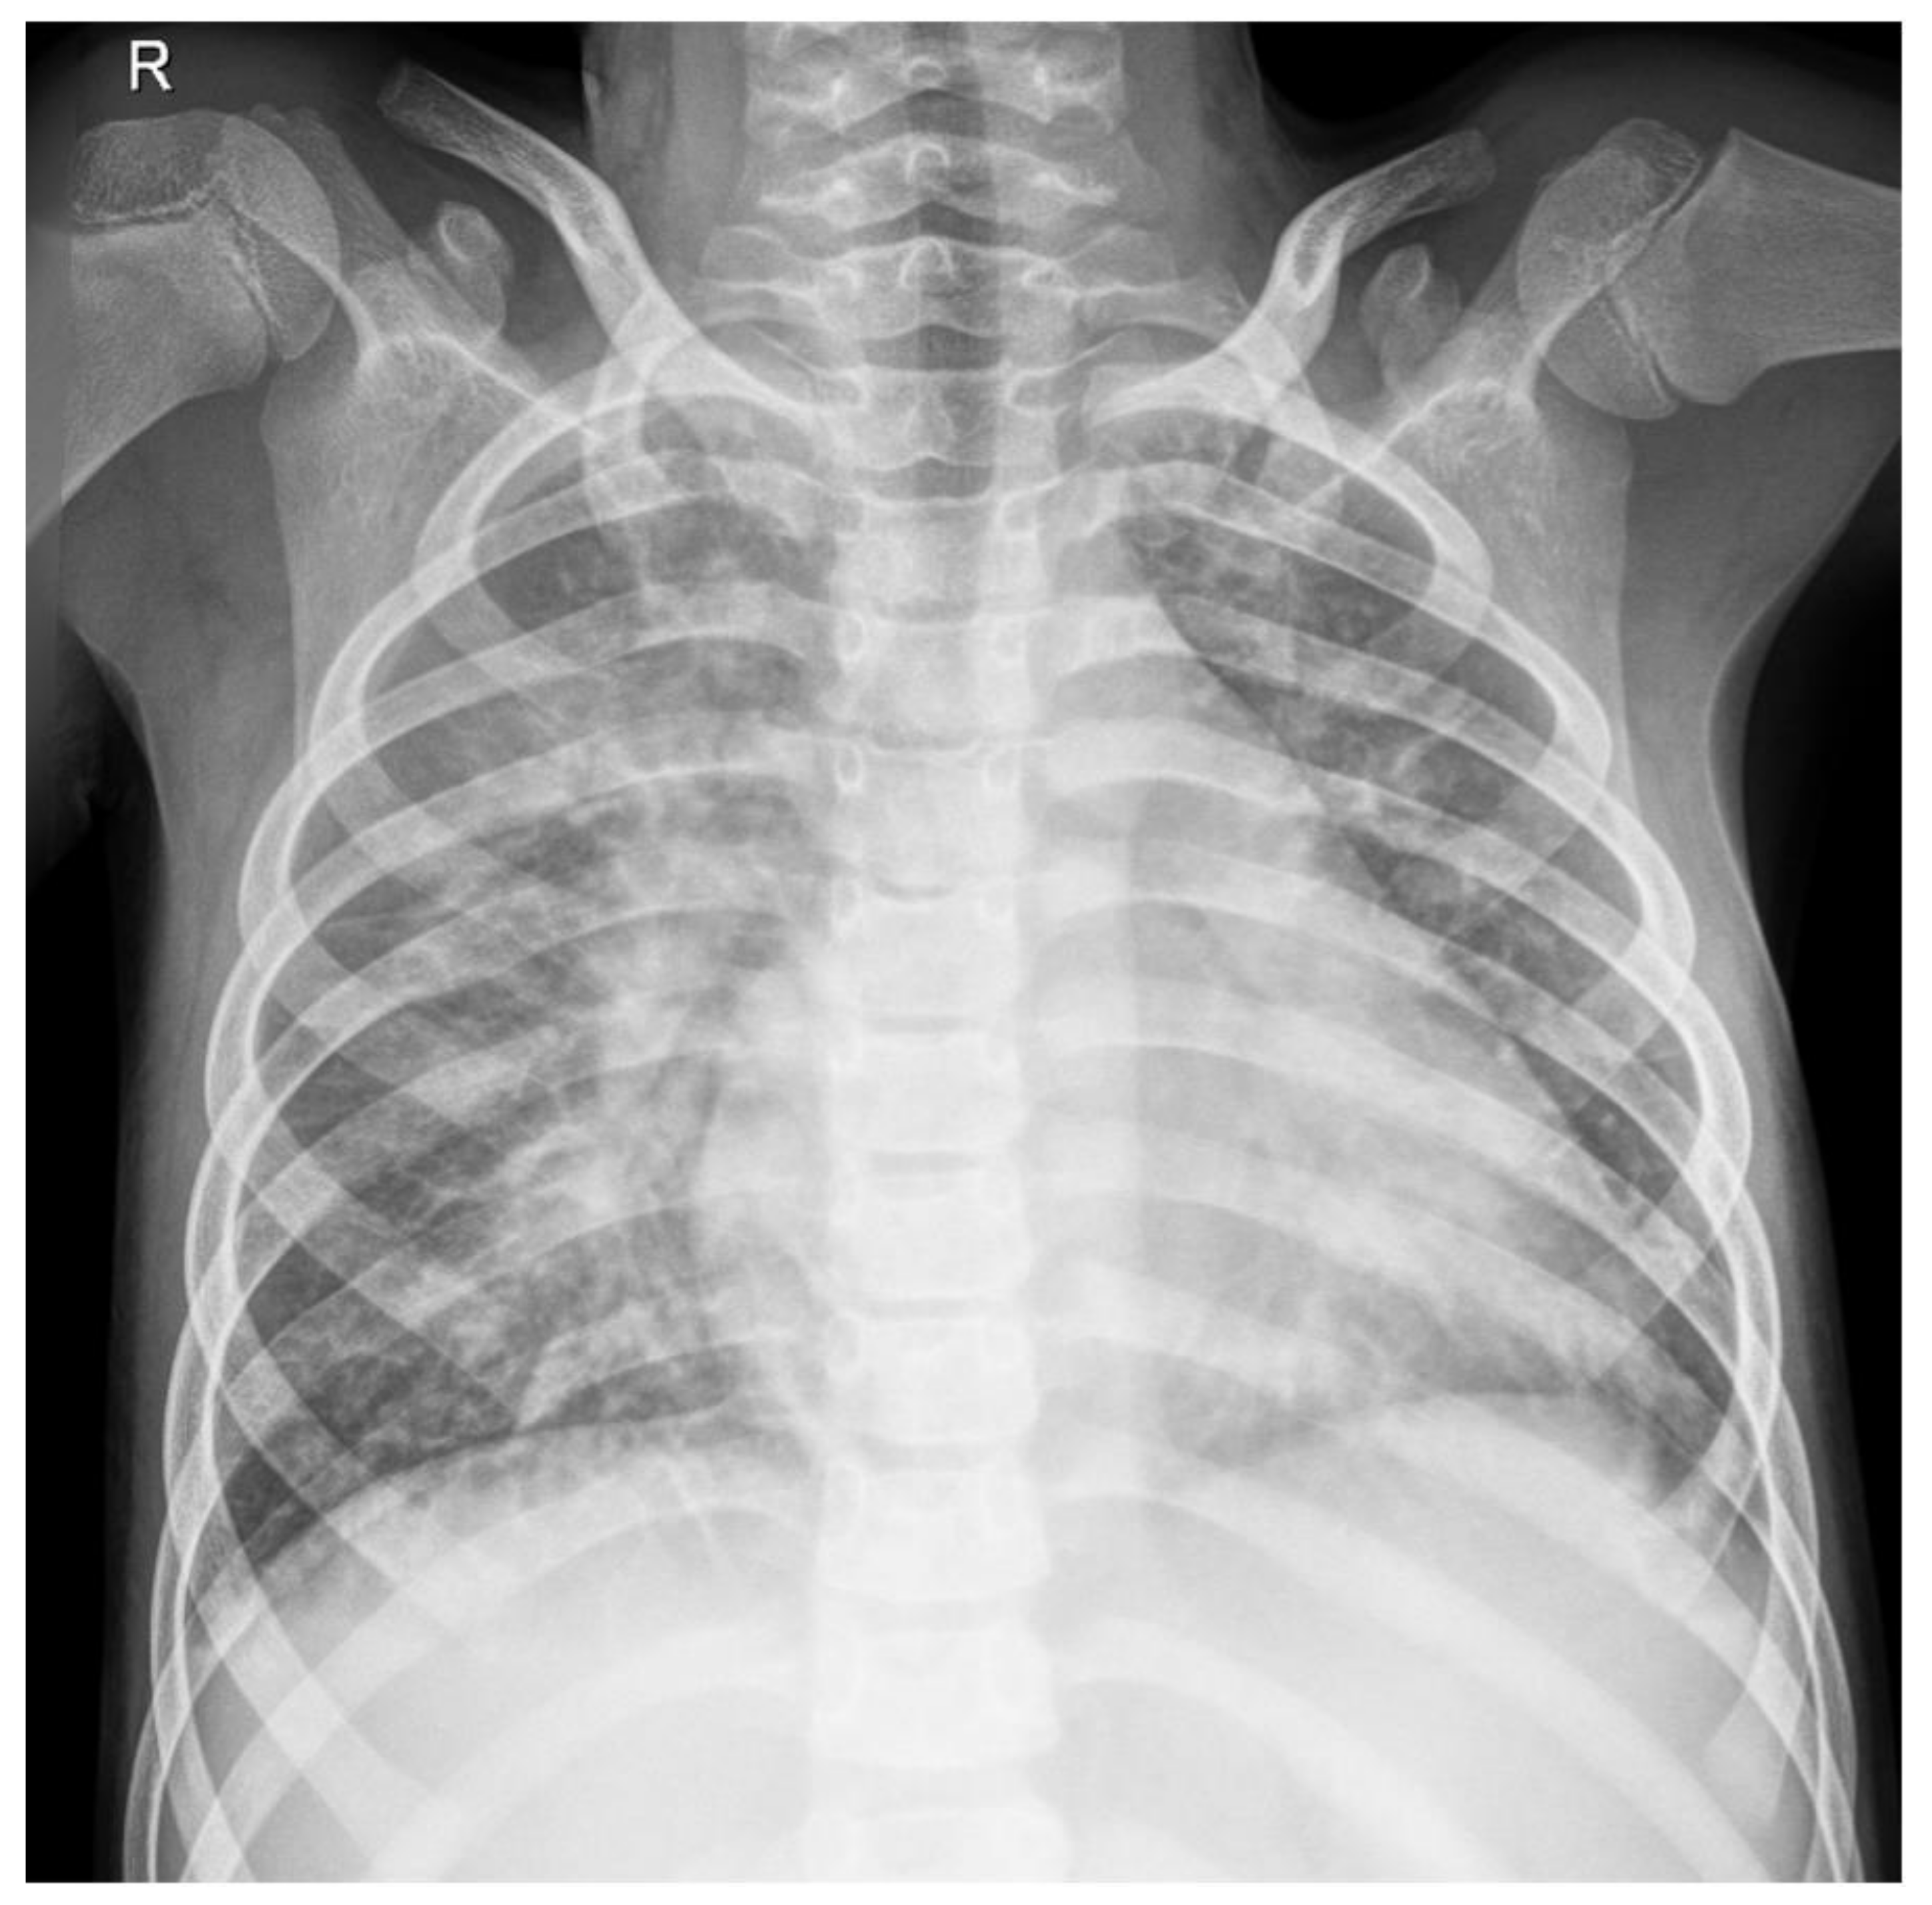

2. Case Report